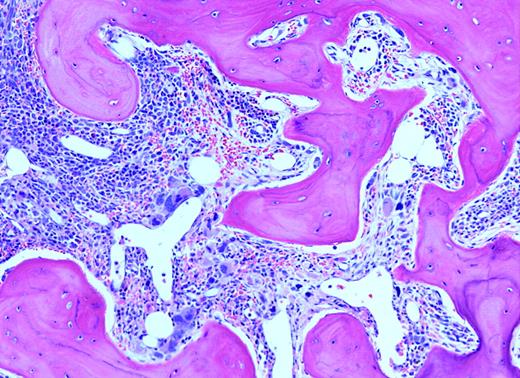

A patient with marked splenomegaly, agnogenic myeloid metaplasia (myelofibrosis with myeloid metaplasia).

Because of the lack of precision in defining response, any codified effort evaluating therapeutic effect is to be applauded. The present effort of the advisory board of the consensus conference (ABCCs) by Barosi and colleagues is a laudable beginning. It is noted that from a standpoint of writing response guidelines, they are based upon “physicians' consensus judgement,” which is an expert opinion, not evidence based. The authors state that defining response is a complex issue, with which I agree. Their proposal basically offers a number of parameters that can be evaluated so that those interested in the treatment of this disease may readily communicate with each other, much like the tumor-node-metastasis (TNM) staging used in cancer. Yet, except for the changes in the bone marrow, many drugs will affect the white blood cell count (WBC), platelet count, hemoglobin, and spleen size without affecting marrow histologically or overall life-span. Thus, relatively minor changes will be considered “drug response” by these criteria. They correctly point out that monitoring changes in bone histology is not routine in either clinical practice or in clinical trials. This is true even in recent publications. Simplified and reproducible scoring systems for fibrosis are much needed. Whatever restores normal marrow histology is the sina qua non of therapy. I am impressed by the basic requirement of a “representative biopsy” defined as artifact free and at least 1.5 cm in length. This will require not only improvement in our hematopathology laboratories, but will also require tempered steel biopsy needles and a hematologist with a mighty arm. Likewise, many aspirations, even in early-stage disease, yield dry taps, making marrow cytogenetic analysis impossible. Perhaps one or another peripheral blood fluorescent in-situ hybridization (FISH) test for more common cytogenetic abnormalities can be considered.FIG2